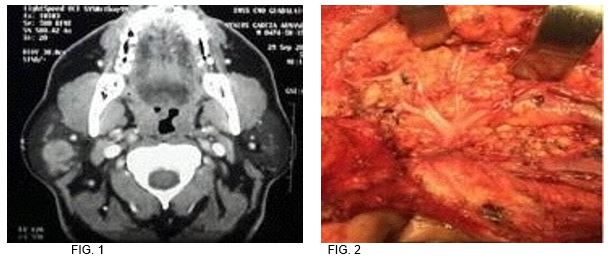

Caso 1: Masculino 49 años de edad, antecedente de tabaquismo e hipertensión, tumor parotídeo derecho de 5x3.5x2.5 pétrea. fue sometido a parotidectomía supraneural, resultando en melanoma maligno nodular con patrón sarcomatoide. (FIG. 1-2)